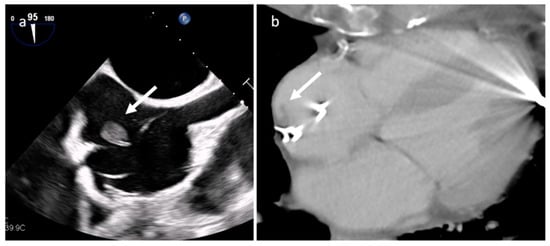

4.2. Papillary Fibroelastoma (PFE)

| Papillary fibroelastoma | Adulthood | Valves | Usually, asymptomatic. Rarely embolic events | Atrial side of the mitral valve or the aortic surface of the aortic valve leaflet | Stippling and vibration or shimmer of the peripheral edge. | Hypodense, smooth, peduncolated, attached to the valve leaflet by a short pedicle | Iso T1w, Hyper T2w, hypo cine with surrounding turbolent flow, poor LGE |